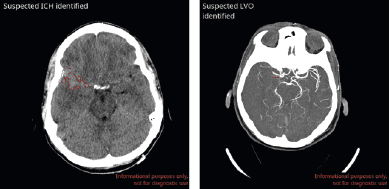

Michael Marx nos presentó la empresa de Inteligencia Artificial fundada el año 2018, Avicenna, la cual ofrece soluciones de Inteligencia Artificial en Radiología de Emergencia Neurovasculares. Su misión es desarrollar soluciones que permitan acelerar el proceso de toma de decisiones terapéuticas en patologías neurovasculares y patologías toracoabdominales; nos presentan soluciones de IA en hemorragias intracraneales, accidentes cerebro vasculares de tipo isquémico, embolismo pulmonar. CINA Head posee certificación FDA.